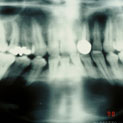

Aunque su estirpe anatomopatológica sea benigna, son quistes que en algunos pacientes provocan grandes destrucciones maxilares, porque crecen de forma asintomática durante años.

Su cirugía es sencilla y está basada en la extracción del quiste con criterios conservadores, y en la reconstrucción del defecto creado por la limpieza quirúrgica.

Para la reconstrucción, aconsejamos hacerlo en la misma intervención y con las bases de ingeniería tisular de la regeneración ósea guiada. Utilizamos como material óseo inductor el fosfato tricálcico tipo beta, mezclado con sangre del paciente y protegido con membrana de regeneración reabsorbible.